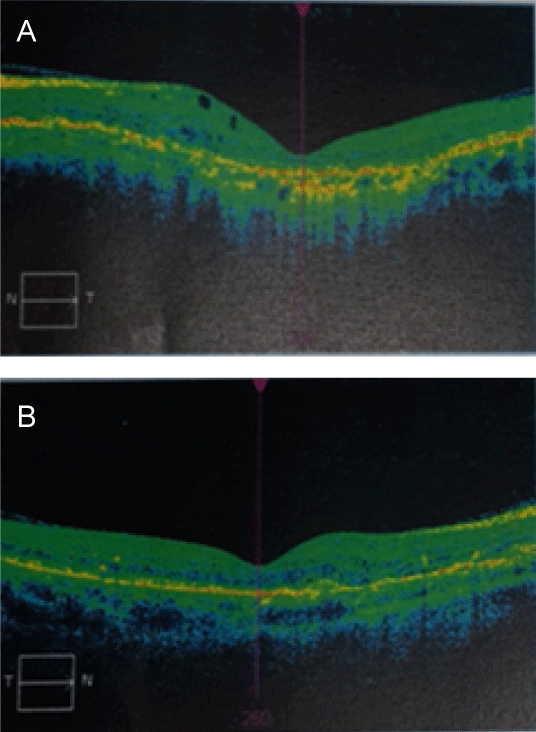

A 50-year-old patient, married with three healthy children, followed by ophthalmology for a progressive reduction of visual acuity and in cardiology for precordialgia. Consulted for yellowish papular lesions and a pseudosclerous, retractile and thickened appearance of the skin of the upper half of the body evolving for 20 years (Figure 1a, Figure 1b and Figure 1c). Cutaneous biopsy showed fragmentation of elastic fibers, variously truncal fibers with loss of their branches, which favors elastopathy. Ophthalmologic examination showed a decrease in bilateral and deeper visual acuity on the left with a normal eye fundus and Optical Coherence Tomography (OCT) demonstrating subretinal choroidal involvement (choroidal neovessels) (Figure 2a and Figure 2b). The cardiovascular examination revealed a blood pressure of 150/90 mmHg with a normal ECG holter and echo heart. The diagnosis of pseudoelastic xanthoma with cutaneous, ophthalmological and cardiovascular involvement was retained.

Figure 2(a,b): Optical Coherence Tomography (OCT) showing subretinal choroidal involvement (neo-choroidal vessels).